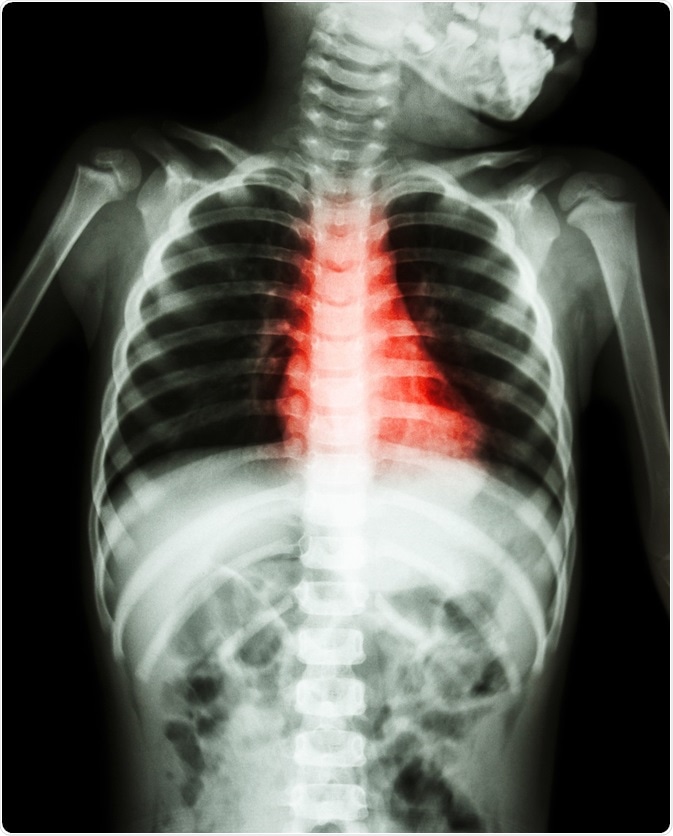

Credit: Puwadol Jaturawutthichai/ Shutterstock.com